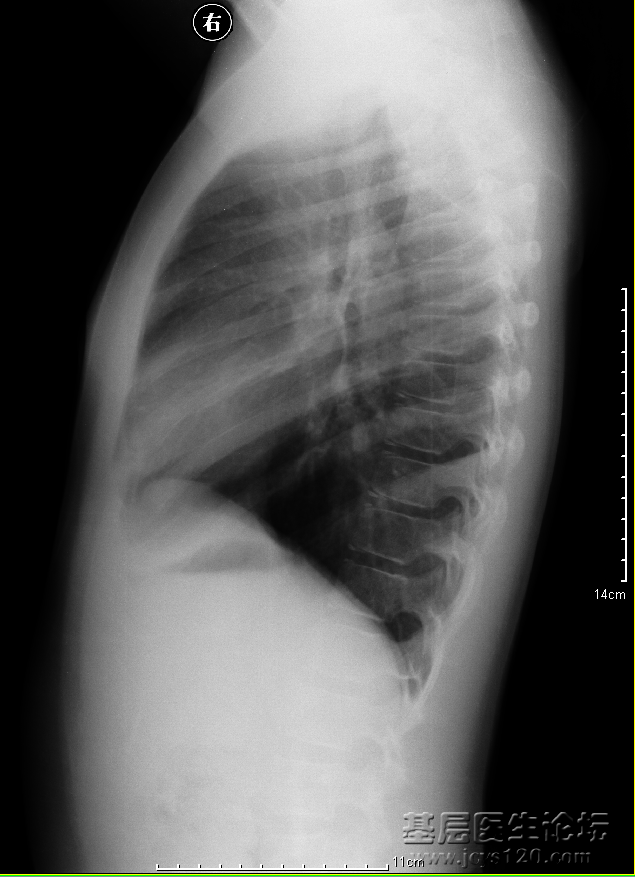

同行帮给看一下这个造影,需要怎么治疗比较理想